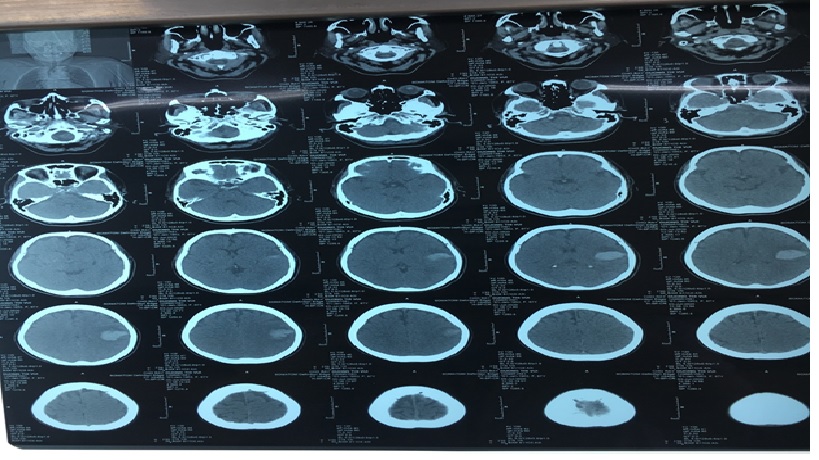

BN được chụp CT đầu không cản quang: XHN vùng trán trái

Chụp CT vùng đầu không có thuốc cản quang

Test nhanh nhất và nhạy nhất để chẩn đoán xuất huyết trong não (ICH), kiểm tra bằng chứng máu trong não thất, hiệu ứng khối và sự dịch chuyển đường giữa